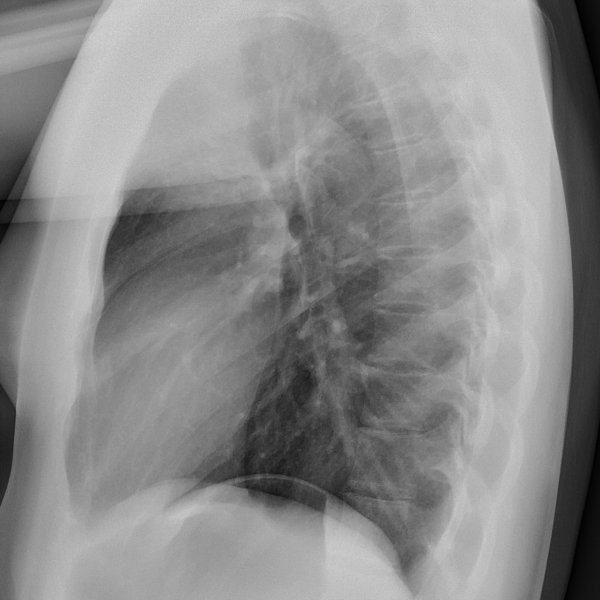

Learn the bony anatomy then test yourself

Learning mode: Hover over the name tags to highlight the relevant anatomy. Once you're ready, head to study mode.

Study mode 1: Click the correct anatomy to match the tag presented.

Study mode 2: Click the correct tag to match the anatomy highlighted.